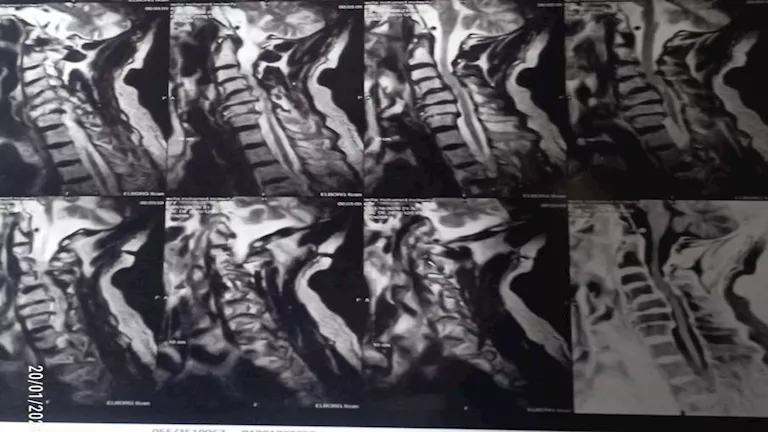

وبإجراء الفحوصات الطبية والأشعات اللازمة، تبين إصابة المريض بانزلاق غضروفي عنقي متعدد على أربعة مستويات، ما أدى إلى حدوث كدمة بالحبل الشوكي وضيق كامل بالقناة الشوكية العنقية، وهي من الحالات شديدة الخطورة التي تستدعي تدخلاً جراحيًا دقيقًا وعاجلًا.

وجرى تجهيز الحالة طبيًا من خلال إجراء جميع الفحوصات والتحاليل اللازمة، قبل أن يخضع المريض لجراحة ميكروسكوبية دقيقة ومعقدة، تم خلالها استئصال الغضاريف المنزلقـة، وتركيب أقفاص عنقية مثبتة بدعامات ذاتية (Stand-alone) على أربعة مستويات، وذلك باحترافية عالية، مع خروج المريض من غرفة العمليات في حالة مستقرة وآمنة.